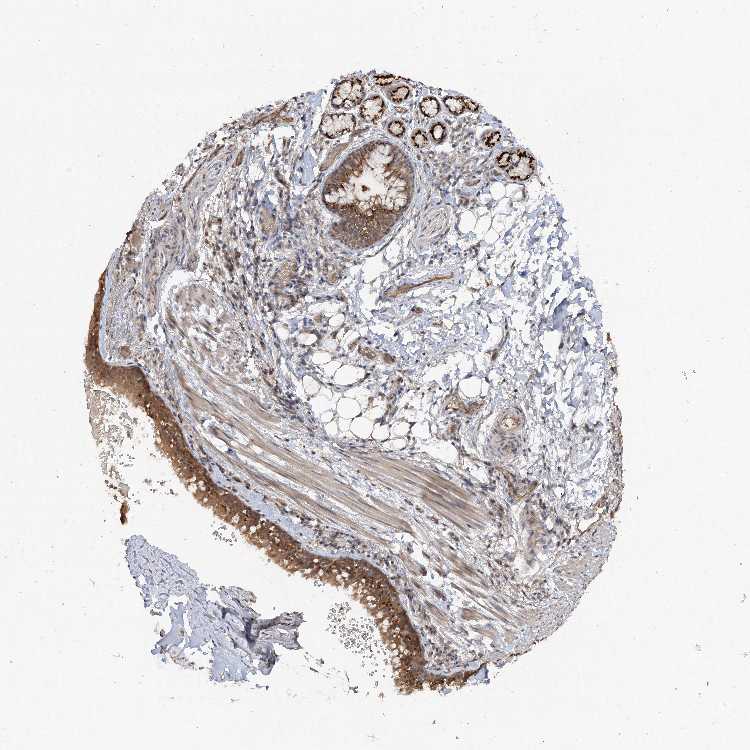

SOFT TISSUE 1 - Antibody stainingi

Antibody staining in the annotated cell types in the current human tissue is reported as not detected, low, medium, or high, based on conventional immunohistochemistry profiling in selected tissues. This score is based on the combination of the staining intensity and fraction of stained cells.

Each image is clickable and will lead to virtual microscopy that enables deeper exploration of all samples and also displays staining intensity scores, fraction scores and subcellular localization as well as patient and tissue information for each sample.

Antibody HPA037384Antibody HPA037385

Fibroblasts LowNot detected

Peripheral nerve Not detectedLow

SOFT TISSUE 2 - Antibody stainingi

Chondrocytes High-